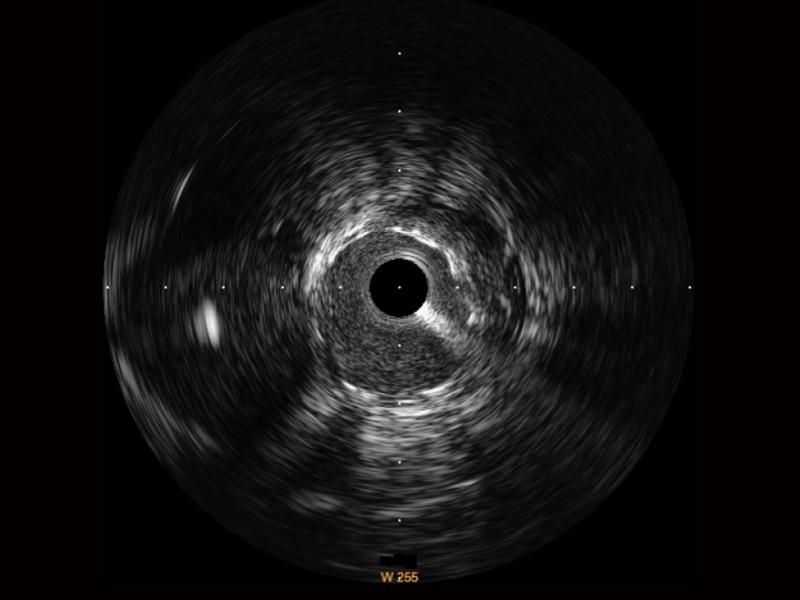

临床图

远场分支血管及导丝

支架内血栓

组织脱垂